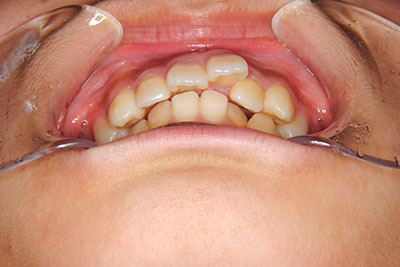

小学生高学年や中高生で矯正治療を考えている方へ

歯が乳歯から永久歯に生え変わった小学生高学年や、中高生でも矯正治療に手遅れということは全くありません。

成長中の顎の骨を矯正できたり、この時期の矯正はおとなになってから矯正治療を始めるよりも短期間で済むことがほとんどです。当院だとおおよそ1年で動的治療(マルチブラケット装置をつける期間)が終わることが多いです。